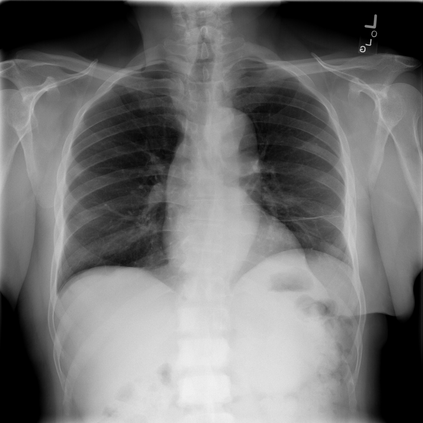

The integration of deep learning systems into healthcare has been hindered by the resource-intensive process of data annotation and the inability of these systems to generalize to different data distributions. Foundation models, which are models pre-trained on large datasets, have emerged as a solution to reduce reliance on annotated data and enhance model generalizability and robustness. DINOv2 is an open-source foundation model pre-trained with self-supervised learning on 142 million curated natural images that exhibits promising capabilities across various vision tasks. Nevertheless, a critical question remains unanswered regarding DINOv2's adaptability to radiological imaging, and whether its features are sufficiently general to benefit radiology image analysis. Therefore, this study comprehensively evaluates DINOv2 for radiology, conducting over 100 experiments across diverse modalities (X-ray, CT, and MRI). To measure the effectiveness and generalizability of DINOv2's feature representations, we analyze the model across medical image analysis tasks including disease classification and organ segmentation on both 2D and 3D images, and under different settings like kNN, few-shot learning, linear-probing, end-to-end fine-tuning, and parameter-efficient fine-tuning. Comparative analyses with established supervised, self-supervised, and weakly-supervised models reveal DINOv2's superior performance and cross-task generalizability. The findings contribute insights to potential avenues for optimizing pre-training strategies for medical imaging and enhancing the broader understanding of DINOv2's role in bridging the gap between natural and radiological image analysis. Our code is available at https://github.com/MohammedSB/DINOv2ForRadiology